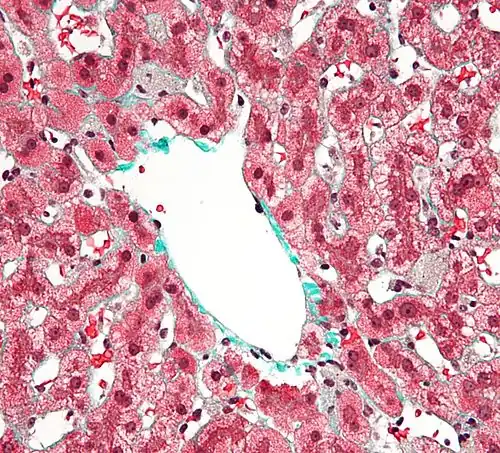

Kupfferovy buňky mají nepravidelný tvar. Jejich cytoplazmatické výběžky (pseudopodia) směřují do lumen jaterních kapilár, ale mohou také prostupovat skrze endoteliální fenestrace do perisinusoidálního prostoru (Disseho prostor, prostor mezi hepatocyty a stěnou sinusů).[4] Pro Kupfferovy buňky je typické velké množství lysozomů a pinocytických váčků a dobře vyvinuté organely důležité pro sekreční aktivitu buněk (endoplazmatické retikulum, Golgiho aparát).[1]